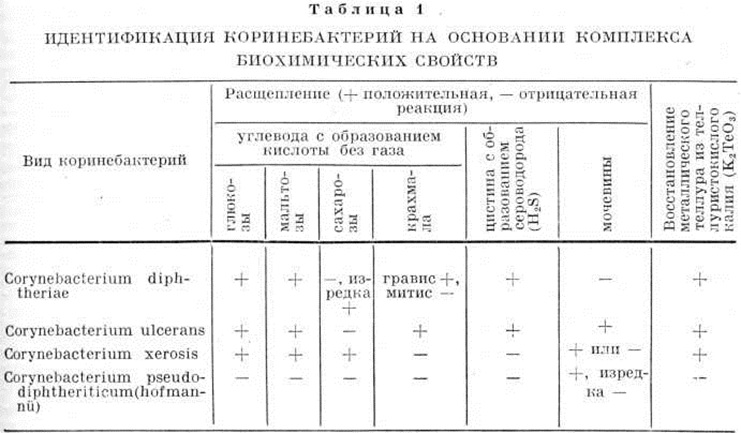

Для роста Cor. diphtheriae применяют питательные среды, приготовленные на основе обычных бульонов — мясопептонного (смотри полный свод знаний Бульон мясопептонный), Мартена (смотри полный свод знаний Мартена бульон, пептон), Хоттингера, с добавлением 5—15% сыворотки или гемолизированной крови. В конце 19 век Э. Ру предложил использовать свернувшуюся лошадиную сыворотку; Ф. Леффлер перед свёртыванием добавлял к ней 25% бульона, содержащего 1% глюкозы. На поверхности плотных кровяных или сывороточных сред дифтерийные культуры развиваются макроскопически через 18—24 часа. Колонии круглые, 0,5—1,0 миллиметров в диаметре, суховатые, кремовато-жёлтого цвета, не сливающиеся даже при сплошном посеве, иногда крошатся при прикосновении петлёй. Cor. diphtheriae расщепляет без газа с образованием кислот глюкозу и мальтозу, изредка сахарозу, а некоторые разновидности — крахмал, гликоген и декстрин. Наиболее постоянным признаком для всех штаммов Cor. diphtheriae является расщепление цистина с образованием H2S, а также отсутствие ферментов уреазы и фосфатазы. Способность коринебактерий Дифтерия и некоторых других восстанавливать металлический теллур из его солей также используется в целях дифференциальной диагностики. Важно, что теллуриты К и Na являются не только субстратом восстановления, но и ингибиторами микрофлоры, встречающейся в зеве.

Вид Cor. diphtheriae неоднороден. Он подразделяется на токсигенные и нетоксигенные разновидности, а также на различные культурально-биохимический, серологические и фаготипы. Выделяют два основных культурально-биохимический типа: гравис и митис, а также ряд промежуточных форм — тип интермедиус [Андерсон (J. S., Anderson) с соавторами, 1931, 1933] и тип минимус (Фробишер, 1946). Наиболее чётко типы дифференцируются по форме колоний на среде Мак-Лауда — варианте кровяного теллуритового агара. Колонии типа гравис (цветной рисунок 3) через 48—72 часа роста имеют диаметром 1,0—2,0 миллиметров, волнистые края, отличаются радиальной исчерченностью и уплощённым центром, напоминают цветок маргаритки. Цвет их благодаря восстановлению теллура и соединению его с одновременно образующимся сероводородом (H2S) серо-чёрный, поверхность колоний матовая. На бульоне представители типа гравис растут в виде крошащейся плёнки. Ок. 90% штаммов расщепляет крахмал, декстрин и гликоген с образованием кислот. Второй биотип — митис — на поверхности кровяного теллуритового агара формирует круглые, слегка выпуклые, черные, матовые колонии, нередко окружённые валиком с ровными краями, диаметром 1,0—2,0 миллиметров (цветной рисунок 4); на бульоне растёт обычно в виде равномерной мути. Большинство штаммов не ферментирует крахмал, декстрин и гликоген. Колонии типа интермедиус круглые и выпуклые, мельче, чем у типа митис, не имеют валика, черные, с блестящей поверхностью; отношение к крахмалу и другим полисахаридам непостоянное. Все биотипы продуцируют идентичный токсин, хотя токсигенность присуща типу гравис. Обозначения типов были введены англ. авторами (Андерсон с соавторами, 1931), полагавшими, что гравис ассоциируется с более тяжёлыми, а митис — с более лёгкими формами болезни. Последующие наблюдения не смогли подтвердить чёткой связи между биотипами и формами заболевания Дифтерия, а также степенью их эпидемиологической опасности.

На поверхности сред в чашках через 24—48 часов появляются хорошо развитые колонии бактерий Дифтерия (цветной рисунок 5), которые используют для выделения чистых культур с целью последующей идентификации (смотри полный свод знаний Идентификация микробов). Установление принадлежности культуры к роду коринебактерий проводится на основании морфологически и культуральных особенностей; идентификация вида Cor. diphtheriae — на основании комплекса биохимический свойств (способности продуцировать H2S на средах с цистином и неспособности расщеплять мочевину). Биотипы гравис и митис различаются по ферментации крахмала с учётом морфологии колоний. Токсигенность определяется in vitro методом преципитации в агаре по Оухтерлоню. Количественное определение степени токсигенности возможно на живых моделях — морских свинках или 9-дневных куриных эмбрионах. Учитывая многообразие тестов и необходимость получения ответа в кратчайшие сроки, наиболее рациональным является следующий порядок действий: выросшая на поверхности элективной среды в чашке хорошо развитая подозрительная колония отсеивается одновременно на среду Леффлера или Ру в пробирку (для получения чистой культуры), на поверхность среды для определения токсигенности (в виде «бляшки») и в столбик среды с цистином. По возможности делают отсевы двух или более колоний. Через 24 часа культуру изучают в микроскопе. При подозрении на принадлежность к роду коринебактерий учитывается результат на среде с цистином (проба Пизу; цветной рисунок 2) и ставится проба на уреазу. На этом этапе (то есть через 48 часов от начала исследования, если не применялся метод обогащения) возможна выдача окончательного ответа. К этому же сроку могут появиться линии преципитации на среде для определения токсигенности; в случае их отсутствия результаты определяются ещё через одни сутки (то есть через 72 часа от начала исследования). Выросшая культура бактерий Дифтерия используется для определения биотипа, серотипа и фаготипа.

Биохимические свойства Cor. diphtheriae и близких к нему видов коринебактерий, встречающихся на коже и слизистых оболочках человека, приведены в таблица 1.